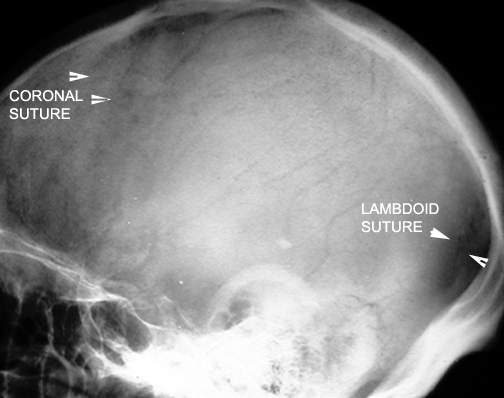

Identify the sutures seen. Click the image for labeling.